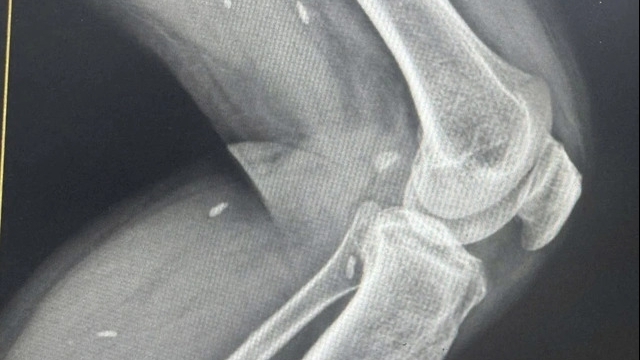

"Cháu bé có một số chỗ trượt da và đã tử vong trước khi tôi dùng tay kéo ra ngoài. Lúc kéo ra cổ cháu có vết đứt dài 8 cm, phải khâu 8 mũi", bác sĩ Đức nói.